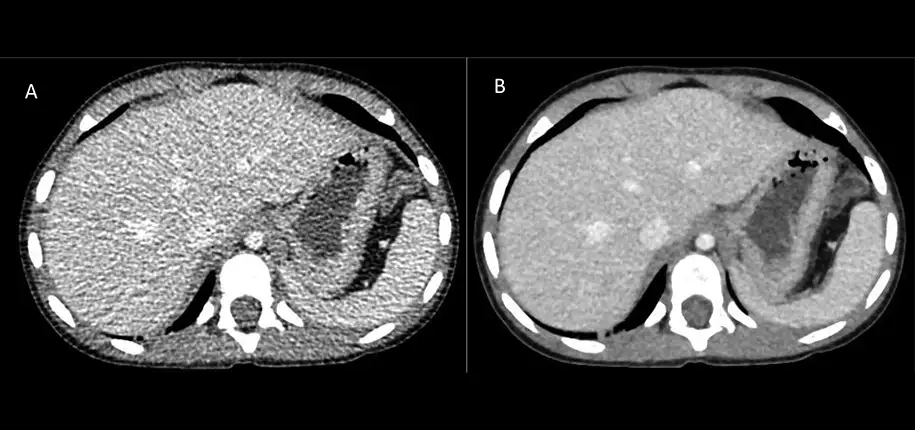

One such example has recently been implemented in the Radiology clinic at Cincinnati Children’s. Over the last year, physicians and scientists at the hospital have been actively working with the manufacturer of our Computed Tomography (CT) scanners to help develop an Artificial Intelligence (AI) computer software that improves the diagnostic quality of the images acquired on the CT scanners in the hospital. This technology has been trained to find areas of low-image quality, such as areas of excessive image noise or clutter, and remove that overlying clutter so that radiologists have a view of the underlying pathology and anatomy. In essence, this technology has been trained to “clean up” the images and present a better version of the image for higher diagnostic confidence.

After years of testing and development, this software was recently installed on CT scanners at the Liberty and Burnett campuses. The introduction of the new AI-driven CT image reconstruction software has immediately improved overall image quality and further improved the safety of these scanners. This new AI technology adds to the further progression of technological advances that are being pursued and investigated at Cincinnati Children’s.